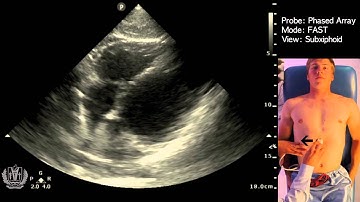

How To: EFAST - Subxiphoid View 3D Video